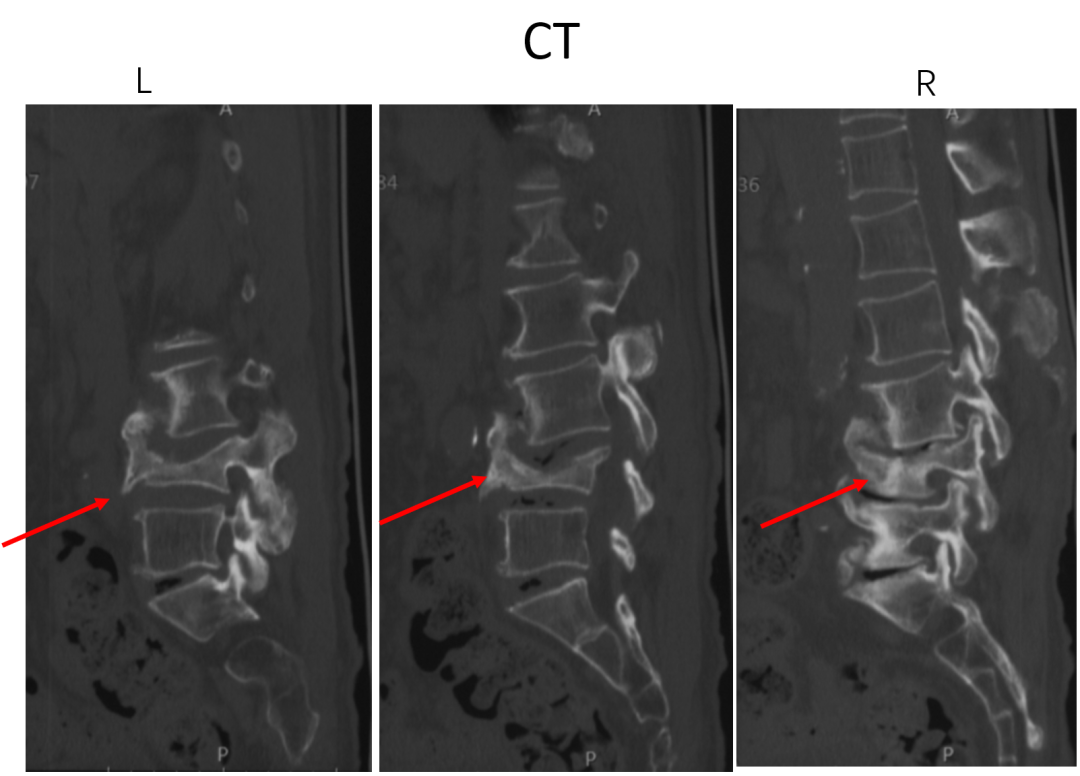

讨论主题:L4压缩骨折伴脊柱侧后凸畸形

影像资料:

腰椎侧后凸畸形

腰椎陈旧性压缩性骨折(L4)